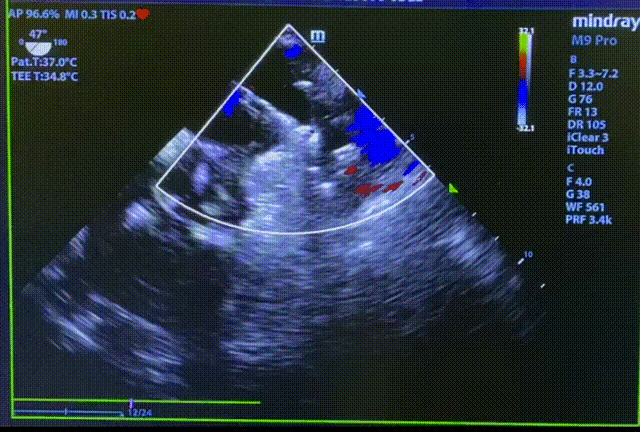

常规肝位造影显示,左心耳锚定区约26mm, 开口约29mm, 因此选择型号为LT-LAA-2834的LAmbre™左心耳封堵器对患者实施封堵。LAmbre™植入过程一步到位,U型钩均完全展开。随后复查造影及TEE结果,封堵盘呈“碗状”形态完美贴合于左心耳口部,无残余分流,牵拉测试稳定,综合评估符合COST原则,随后完美释放,封堵效果理想。术后,患者各项指标正常,身体恢复良好。

封堵器释放后头位与肝位造影

释放后TEE检查(135°)